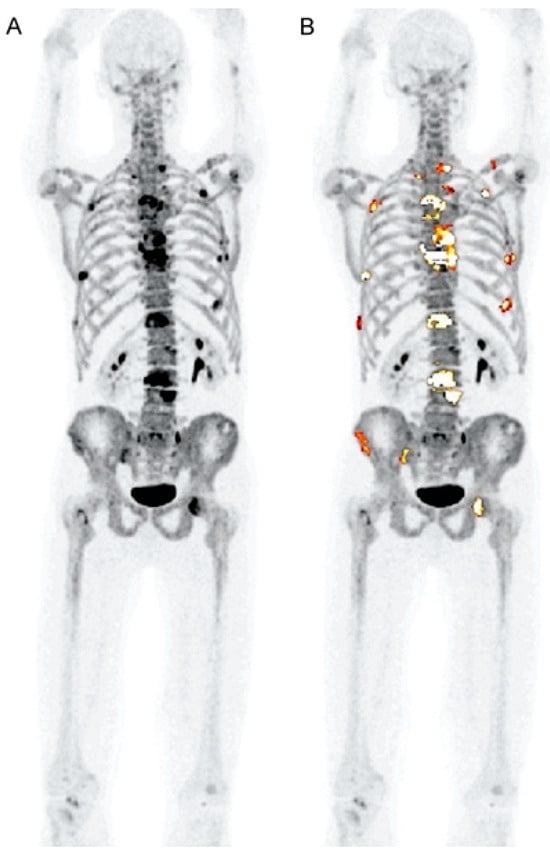

Certain research teams have recently proposed using CT-based segmentation to analyze the uptake of radiotracers in the bone marrow and the overall bone structure of myeloma patients as an alternative to concentrating solely on specific osteolytic lesions [23] (Figure 10 and Figure 11). These approaches have demonstrated a high level of reproducibility [23] (Table 1). However, the clinical significance of these methods still needs to be investigated further [23]. This method has recently been used by the Penn–Odense group to assess the uptake of [18F]FDG in the context of dual-time-point imaging (Figure 12) [35]. Pre-treatment [18F]FDG PET/CT scans from 36 patients with MM were collected [35]. These scans were conducted at 1 and 3 h after the injection of the tracer. A segmentation and quantification of whole-bone marrow (WBM) [18F]FDG uptake was performed using a threshold algorithm utilizing Hounsfield units obtained from CT data [35]. The patients were split into two treatment groups: one received non-HDT, and the other received HDT with ASCT. The international response criteria were utilized to assess the treatment outcomes for each multiple myeloma patient. In the group that underwent HDT, there was a notable increase in WBM [18F]FDG uptake among patients who responded poorly to treatment (Figure 12) [35]. The median value escalated from 1.31 (with an interquartile range, IQR, of 1.13–1.64) after one hour to 1.85 (IQR: 1.45–2.10) at the three-hour mark, illustrating this increase [35]. The calculated median percentage alteration ranged from 6.10% to 50.73% (IQR: 23.47–46.4; p = 0.003). In contrast, there was no apparent change in uptake for patients exhibiting a complete response (p = 0.24) (Figure 12). A similar pattern was observed in the non-HDT group [35].

Figure 10.

This figure demonstrates the potential role of global disease assessment by PET in MM. It shows changes in [18F]FDG uptake in MM lesions before (A) and after treatment (B). High diffuse [18F]FDG uptake is visible across the entire spine before treatment (A), whereas a substantial reduction in [18F]FDG uptake can be visually observed after treatment (B). Segmentation of the entire skeleton followed by a closing algorithm allows for a global disease assessment (C,D). The pre-treatment global average SUVmean (C) was 3.1 and decreased to 1.8 after the completion of the treatment (D). The image was sourced from PMID: 31084774 (Figure 4), and permission was granted for its use.

Figure 11.

This presents the whole-body [18F]FDG PET and combined [18F]FDG PET-CT images of a 60-year-old man diagnosed with multiple myeloma. The entire skeleton was segmented by employing an iterative threshold algorithm based on Hounsfield units, followed by a smoothing and closing procedure. This method yields the global SUVmean (GSUVmean), which represents the total bone marrow involvement in patients with multiple myeloma. (A) Prior to treatment commencement, the GSUVmean was 2.02. However, (B) upon completing the treatment, the GSUVmean significantly decreased to 1.10. The image was sourced from PMID: 30420215 (Figure 6), and permission was granted for its use.